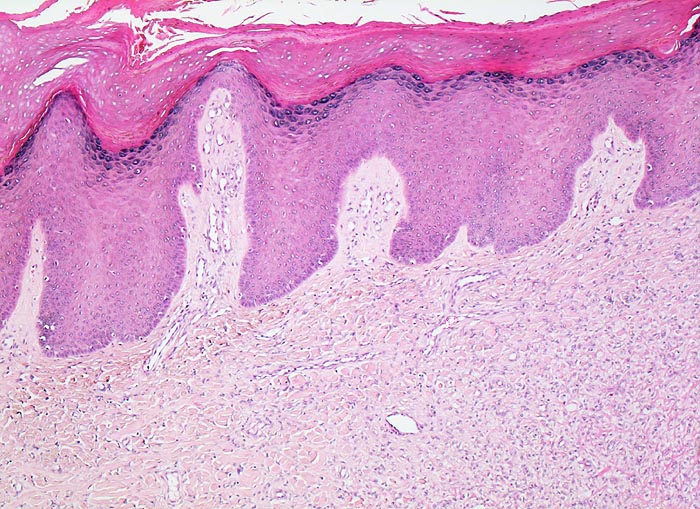

Die Epidermis über dem dermal lokalisierten Tumor zeigt eine Hyperplasie (> 7793) oftmals mit basaler Hyperpigmentierung PathoPic 7803. Histologisch besteht das Histiozytom aus einem Spektrum von Zelltypen mit Merkmalen von dermal dendritischen Zellen, (Myo)fibroblasten und Histiozyten. Zusätzlich können Entzündungszellen, fettspeichernde Tumorzellen mit schaumigem Zytoplasma, eisenpigment (Hämosiderin) speichernde Tumorzellen (> 7718) oder mehrkernige Riesenzellen vorhanden sein. Charakteristisch ist eine wirblige/sternförmige Anordnung von Spindelzellen und Kollagenfasern (=storiformes Wachstumsmuster). Kollagengehalt (> 219) und Zellgehalt (> 3967) sind von Tumor zu Tumor sehr unterschiedlich. Frühe Läsionen sind zell- und gefässreich, spätere zeigen eine vermehrte Fibrosierung und als Folge von Einblutungen Ansammlungen von lipid- und pigmentspeichernden Tumorzellen. Histiozytome können sehr zellreich (> 3968) oder sehr zellarm sein. Sehr charakteristisch ist die unscharfe Begrenzung des Tumors zum dermalen Bindegewebe mit Einschluss kompakter Kollagenfasern innerhalb des Tumors und Ausbreitung von einzelnen Tumorzellen zwischen die tumorangrenzenden Kollagenfasern.

• Epidermishyperplasie (Akanthose) und Hyperpigmentierung der basalen Keratinozyten über dem Tumor.

• Unscharf begrenzter dermaler Tumor ohne direkten Kontakt zur Epidermis.

• Im Tumor eingeschlossene kompakte Kollagenfasern und am Rand des Tumors Ausbreitung von Tumorzellen zwischen den dermalen Kollagenfasern.

• Tumor bestehend aus spindeligen (myo)fibroblastären Zellen mit länglichen Kernen in unregelmässiger Anordnung (Zellen mit unterschiedlicher Ausrichtung zueinander), mit storiformer (sternförmig/wirbelförmig) oder faszikulärer (parallel ausgerichtete Zellbündel) Architektur.

• Die charakteristischen Veränderungen der Epidermis helfen bei der manchmal schwierigen Abgrenzung des fibrösen Histiozytoms von anderen dermalen Hauttumoren. Deshalb sollte nach Möglichkeit die Epidermis mitexzidiert werden.